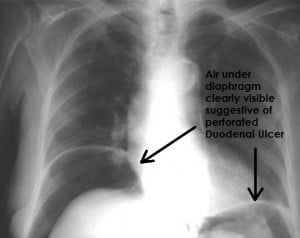

If a peptic ulcer perforates, air will leak from the inside of the gastrointestinal tract to the peritoneal cavity. This leads to “free gas” within the peritoneal cavity. If the patient stands erect, as when having a chest X-ray, the gas will float to a position underneath the diaphragm. Therefore, gas in the peritoneal cavity, shown on an erect chest X-ray or supine lateral abdominal X-ray, is an omen of perforated peptic ulcer disease.

- X-Ray Chest PA view (free gas under the right dome of diaphragm.).